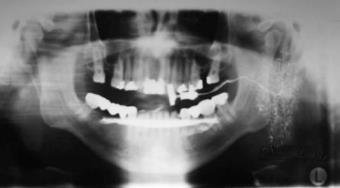

Klinikai tünetek, diagnosztika. A Sjögren-szindróma vezető tünetei a glandularis tünetek: a száraz szem (xerophthalmia vagy keratoconjunctivitis sicca) és a csökkent nyáltermelés okozta szájszáradás (xerostomia). A csökkent könnytermelés szúró, idegentest érzést okoz, szövődménye a szaruhártya fekélye, szemhéjak gyulladása lehet. A csökkent nyáltermelés a betegnek beszéd-, táplálkozási, ízérzési panaszokat okoz. Ezeken kívül gyakori a fokozott caries incidenciája, a nyálkahártya, döntően gombás, gyulladása. Gyakori a nagy nyálmirigyek (főleg parotisok) fájdalmatlan duzzanata. Nincs olyan laboratóriumi eltérés, mely specifikusan utalna a kórképre, de különböző autoantitestek az esetek nagy részében kimutathatók: rheumatoid faktor (RF), antinuklearis antitest (ANA), anti SS-A, anti-SS-B. A szemészeti komponens vizsgálatára a klasszikus Schirmer-teszten kívül a könnyfilm felszakadási időt mérik („Break Up Time”, BUT), illetve a cornea festődését (pl. lissamin zöld alkalmazásával) nézik réslámpával a hámdefektusok kimutatására. A nyálmirigy-érintettség vizsgálata eltérő a különböző diagnosztikus kritériumrendszerekben, a használt módszerek a nyugalmi kevert nyál szekréciójának mérése, szcintigráfia, parotisok ultrahangvizsgálata, szialográfiája (12.11. ábra). Általánosan a legobjektívebbnek a kis nyálmirigyek szövettani vizsgálatát tekintik.

12.11. ábra. Sjögren-szindrómás beteg parotisát ábrázoló szialogram

(Dr. Pataky Levente anyagából)